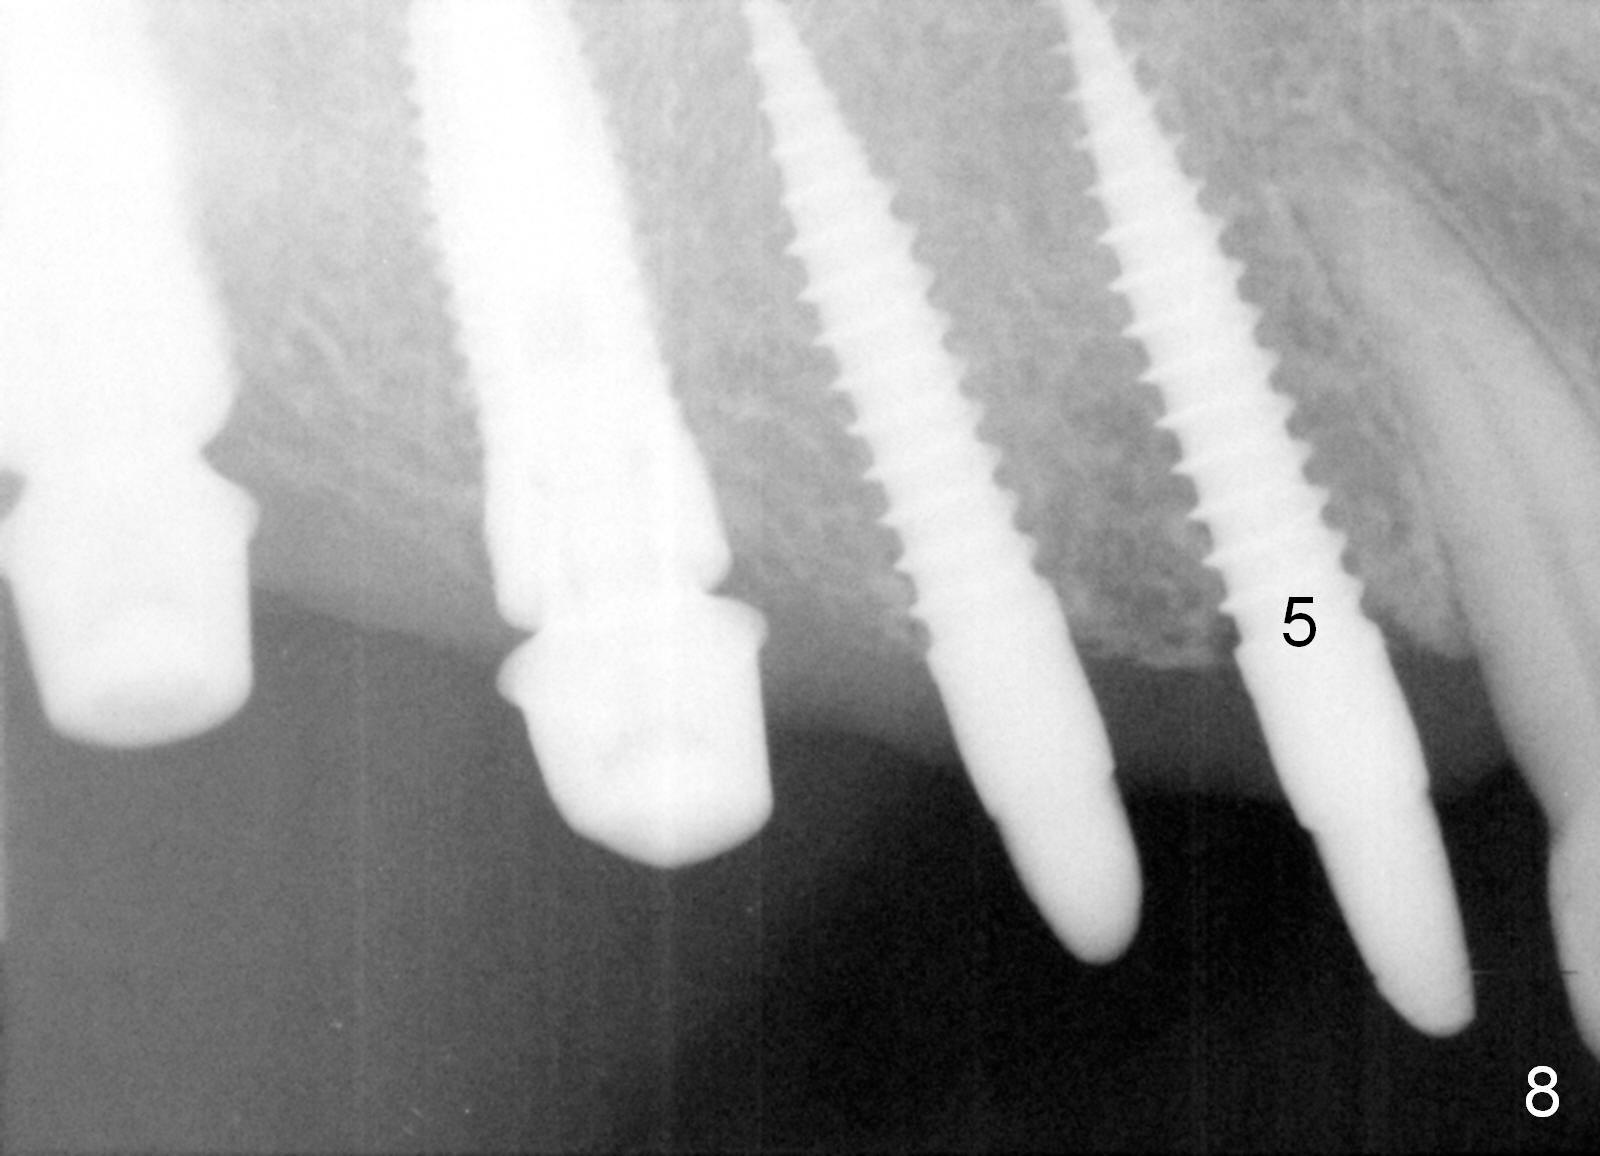

Provisional bridge is fabricated after wound healing.  Four months postop, there is minimal bone resorption at the site of #5 (Fig.7,8).  Single-unit crowns are fabricated.